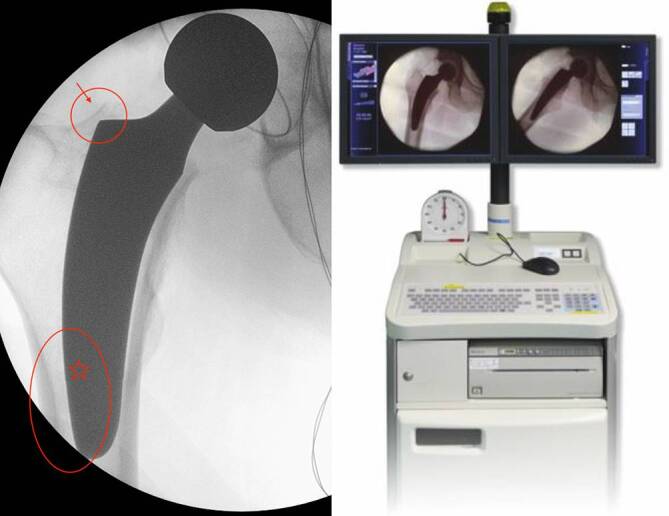

Short stems in total hip arthroplasty are increasingly being established and offer several advantages in terms of minimal invasiveness and bone preservation compared to standard implants. The rounded design and shorter stem length facilitate better adaptation to natural anatomy, at the same time also posing specific risks and complications. When transitioning to short stems, a learning curve must be considered. Careful patient selection and preoperative planning are crucial, and intraoperative imaging is recommended. The most common implant-specific complications include insufficient osseointegration, leading to subsidence and aseptic loosening, as well as periprosthetic fractures. The risk instability and dislocations as well as periprosthetic infections can potentially be reduced with short stems. This article discusses the frequency, causes, and treatment options for these types of complications and highlights current evidence-based treatment approaches.